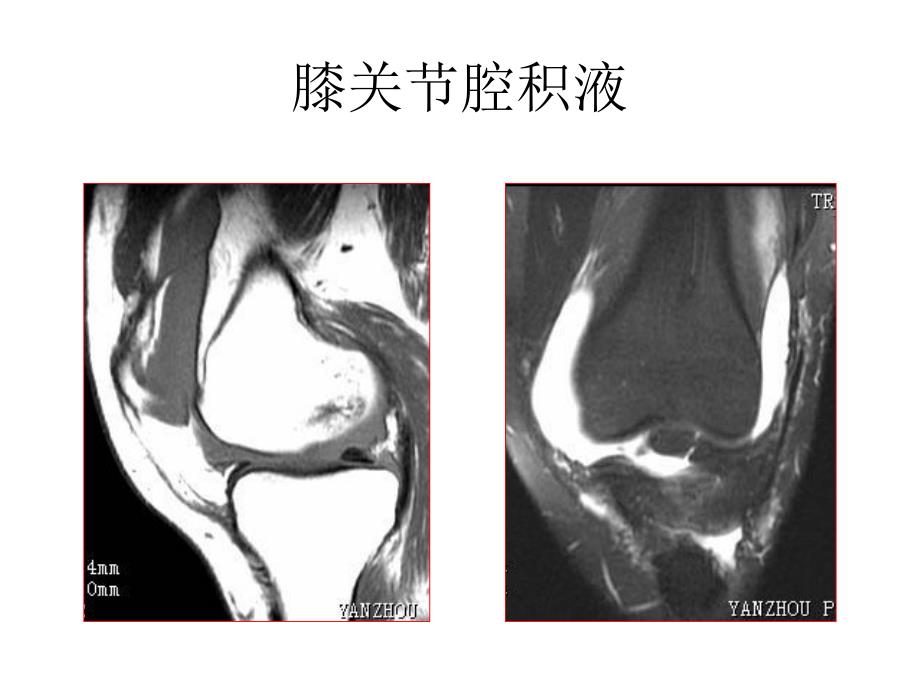

运动骨骼系统膝关节腔积液胫骨平台骨折MR:060677股骨内、外侧髁撕脱骨折胫腓骨粉碎性骨折左耻骨骨折左侧髂骨骨折左侧髋臼骨折 对侧正常跟腱跟腱损伤MR:060574骨肿瘤MR:061365骨软骨瘤CT:41161骨软骨瘤MR:061626肱骨恶性肿瘤MR072389肱骨恶性肿瘤MR072389脊柱、脊髓椎体压缩骨折,双边征C5棘突骨折并椎体前滑脱,C7椎体压缩骨折Sag T2WISag T1WISag fsT2WIC35水平颈髓损伤L1椎体压缩性骨折右侧横突骨折颈椎间盘髓核脱垂腰椎间盘髓核脱垂CE腰椎间盘突出椎管占位,脊膜瘤脊髓室管膜细胞瘤骶管蛛网膜囊肿椎管髓外硬膜内占位拴系综合症MR:060556